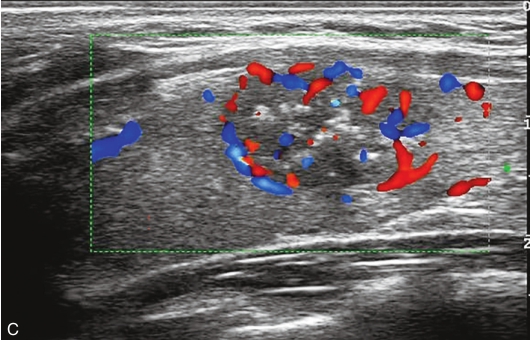

甲状腺右叶中部见一低回声结节,大小约2.0cm×0.9cm×1.7cm,部分边界不清楚,形态不规则,内可见多发点状强回声。CDFI结节内及周边可见较丰富血流信号,见图1-9-7。

图1-9-7 甲状腺髓样癌常规超声声像图

A.甲状腺右叶结节横切面;B.甲状腺右叶结节纵切面;C.甲状腺右叶结节CDFI血流图

甲状腺右叶中部结节超声造影后早于周围组织开始,自周边向中心逐渐增强,达峰时呈不均匀等增强,增强范围较常规超声增大,周边可见不规则环状高增强,结节前方甲状腺被膜连续性中断,之后消退呈明显低增强,见图1-9-8。

图1-9-8 甲状腺髓样癌超声造影图

A.动脉早期;B.达峰时;C.增强晚期

甲状腺右叶中部低回声结节伴有多发钙化,边界不清,形态不规则,血流丰富;超声造影后呈不均匀低增强,周边可见不规则环状高增强结节增强范围较常规超声增大,结节前方甲状腺被膜连续性中断,上述特征均提示恶性。